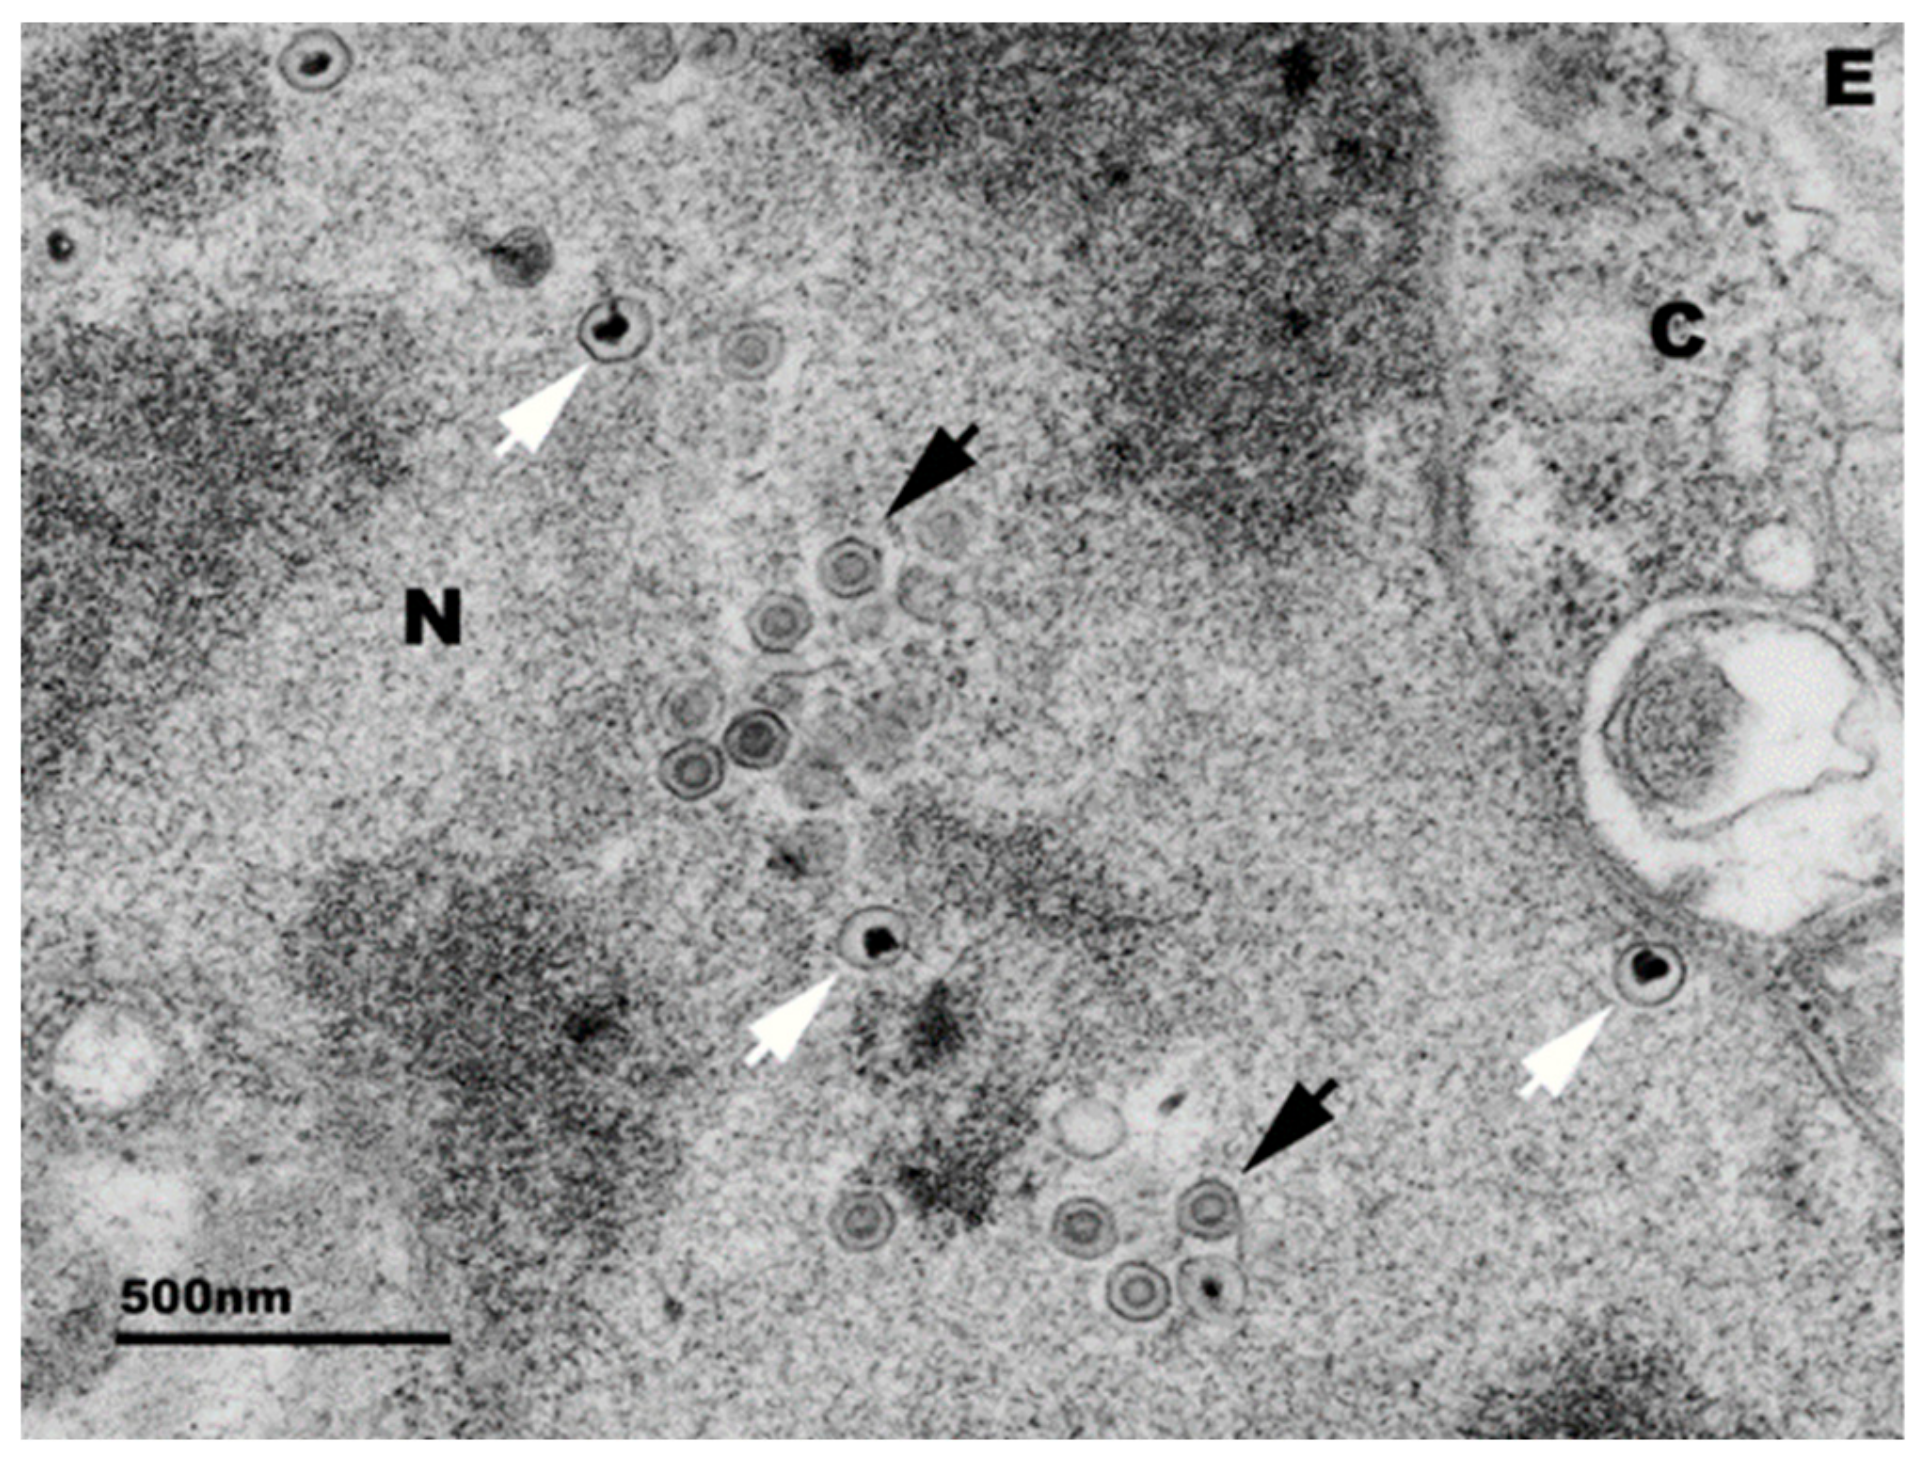

2. Clinical Signs and Pathology

4. Experimental Disease Model

5. Virus-Host Interaction